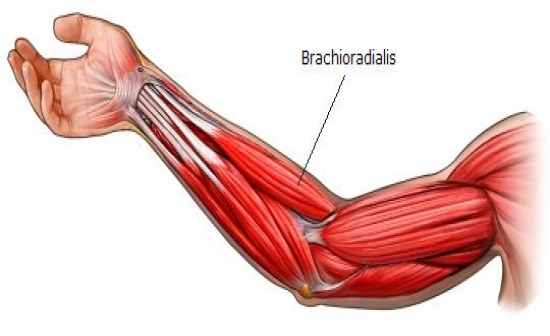

Анатомия и функции мышцы brachioradialis